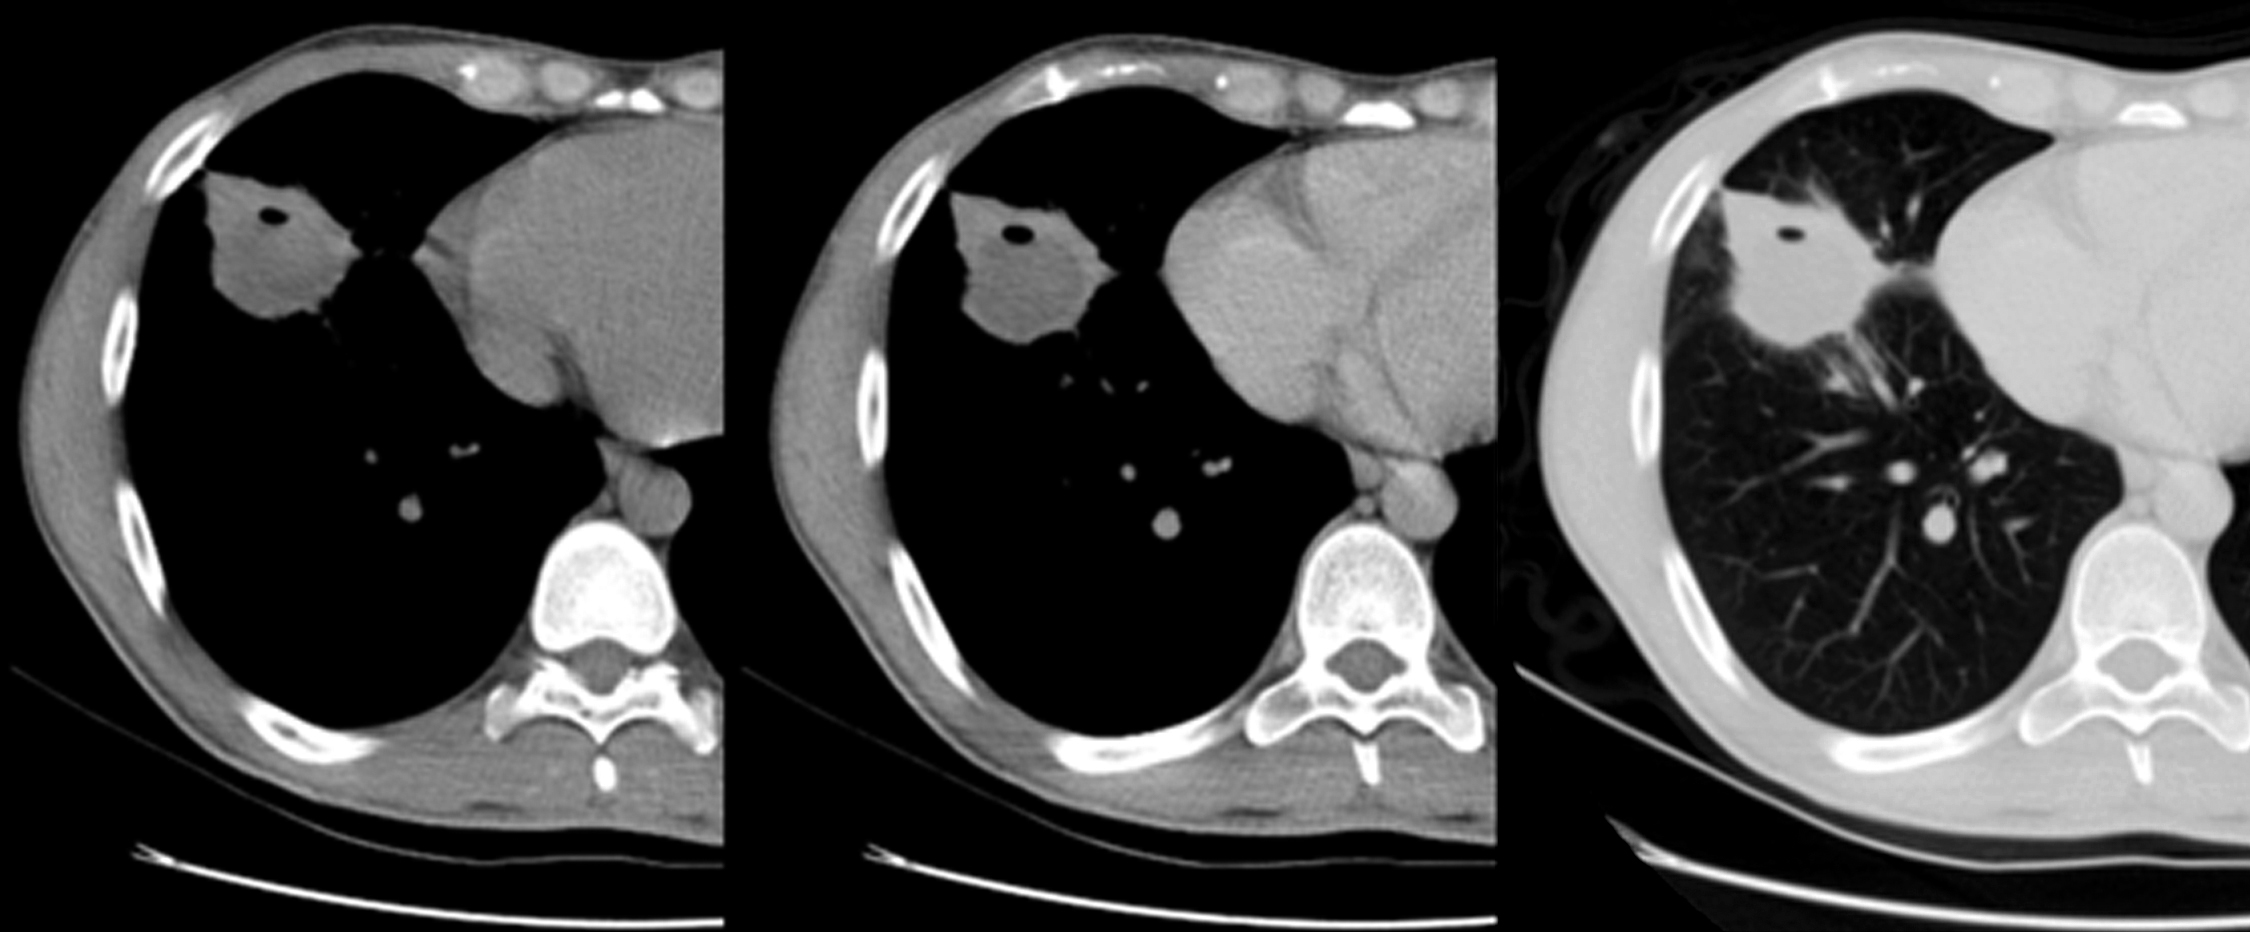

Se solicita radiografía de tórax de frente y perfil (Figura 4) en la que se observa una masa localizada en lóbulo medio, redondeada, bien delimitada, de 4 cm de diámetro mayor, sin otras alteraciones en campos pulmonares y silueta cardiomediastínica.

Figura 4

Radiografía de tórax, proyección PA (a) y perfil (b) donde se observa masa redondeada bien definida situada en el lóbulo medio.

Figura 5

TC de Tórax: cortes axiales en ventana de mediastino previo a la administración de contraste (a), en fase venosa (b) y con ventana de pulmón (c.); en el lóbulo medio y segmento basal anterior del lóbulo inferior derecho se observa masa ovoidea, bien definida, de densidad heterogénea con realce periférico y un pequeño sector cavitado.